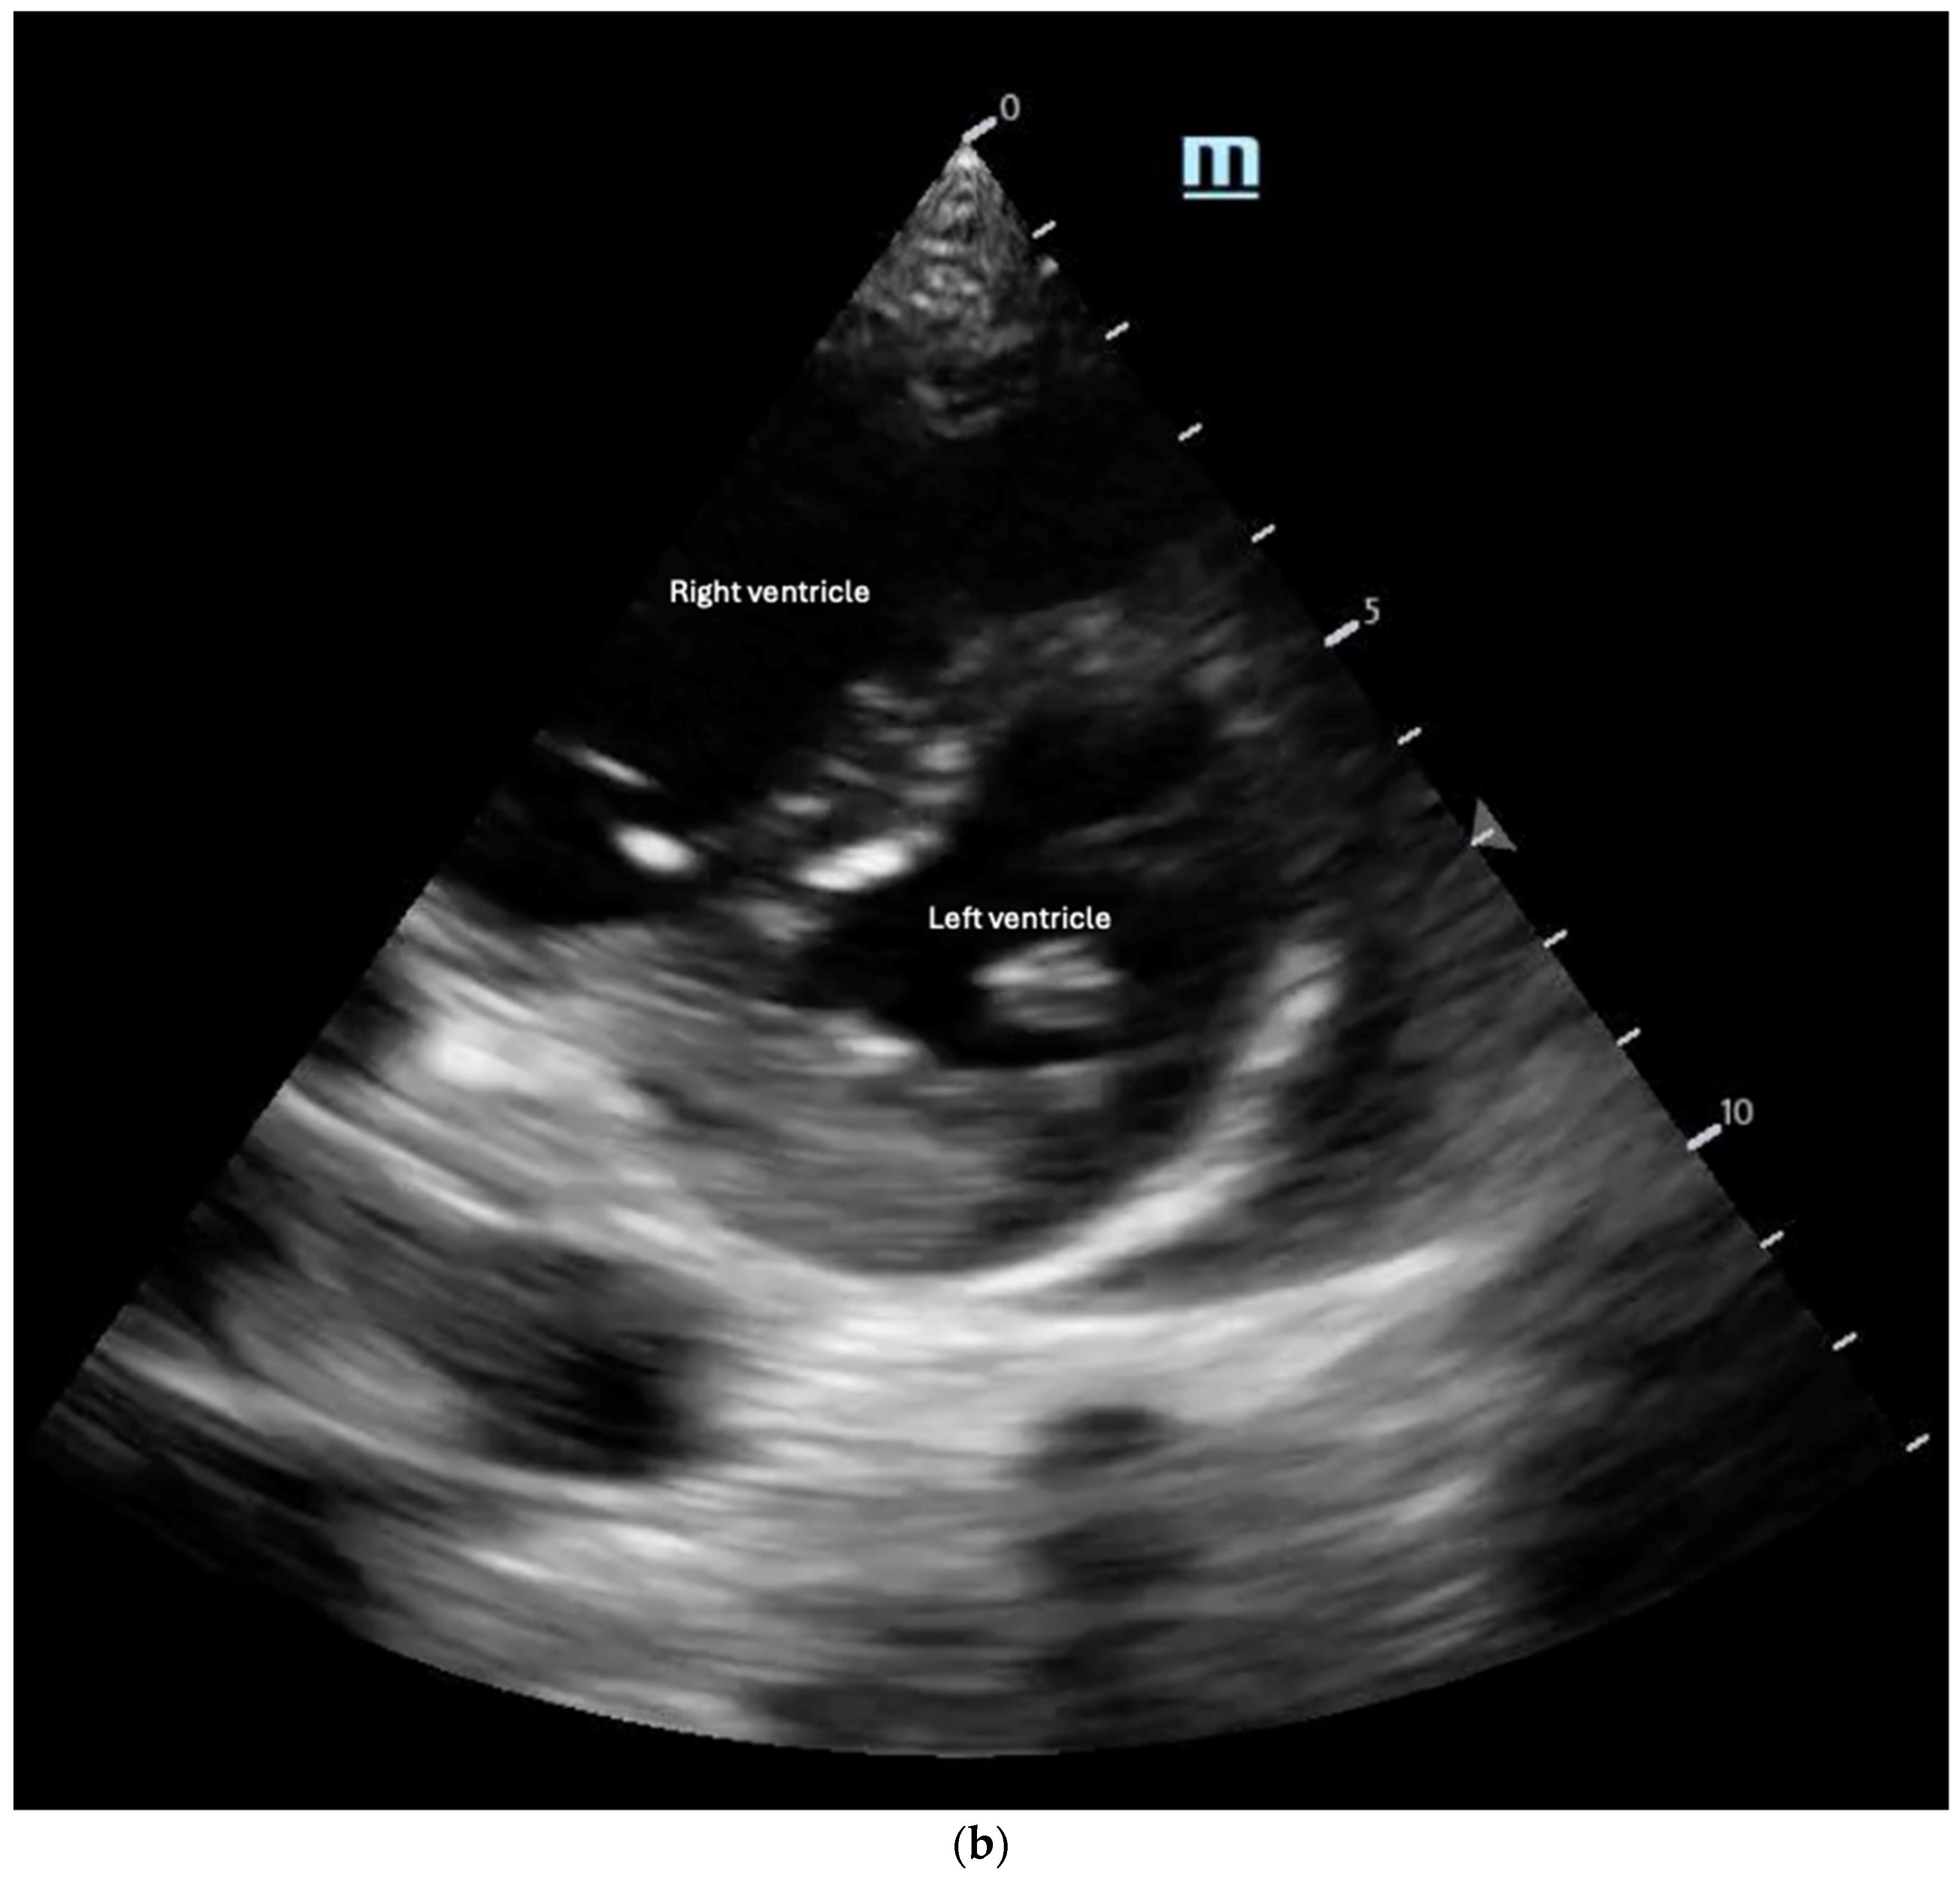

- The “D-Sign”: This refers to the flattening of the interventricular septum with a leftward deviation into the left ventricle, causing the left ventricle to appear as a D-shaped structure, as seen in the parasternal short-axis view (Figure 8b). This finding suggests increased RV afterload and can be associated with pulmonary hypertension, acute PE, and RV failure [35]. Diastolic septal flattening indicates volume overload (e.g., severe tricuspid regurgitation or atrial septal defect), while systolic flattening points to pressure overload (e.g., pulmonary hypertension or acute PE). In volume overload, the D shape is most pronounced at end-diastole and resolves in systole, whereas in pressure overload, flattening persists throughout the cardiac cycle [36].